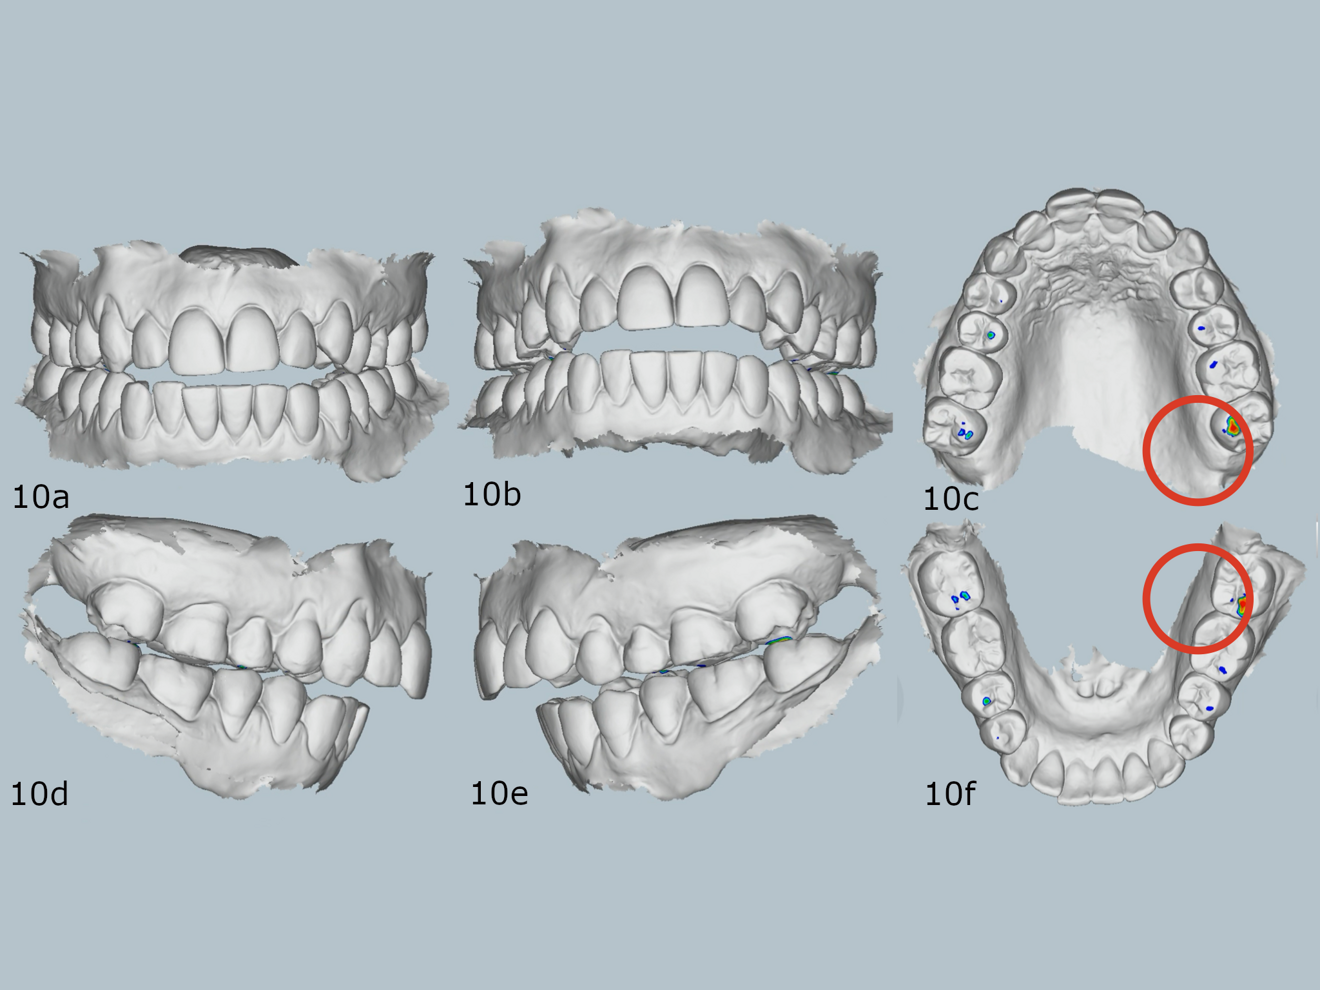

When measuring the size of her teeth and conducting a Bolton analysis, we identified an anterior Bolton discrepancy due to mandibular excess (Fig. 8). In maximum intercuspation, there were bilateral contacts only on the posterior teeth (Fig. 9). In her arc of closure (Fig. 10), a unilateral posterior fulcrum was observed. It was due to premature contact on the maxillary left second molars.

Figs. 10a–f: Relationship at the first contact in the arc of closure.